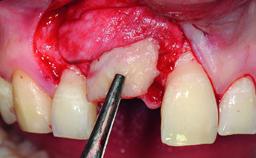

Replacement of an Upper Right Central Incisor with Root Resorption: Ridge Preservation, Early Placement of an RC Bone Level Implant

A 49-year-old female patient was referred for implant therapy to replace the upper right central incisor (tooth 11). The tooth had been assessed by an endodontist who diagnosed a vertical fracture of the root. The tooth had a hopeless prognosis and needed to be extracted. The patient was healthy and was not taking any medications. She was allergic to penicillin. The patient had high esthetic demands but her expectations were realistic. The extraoral examination revealed no facial asymmetries. The right temporomandibular joint demonstrated an opening click but was otherwise asymptomatic. The lip line was high with a significant gingival display.